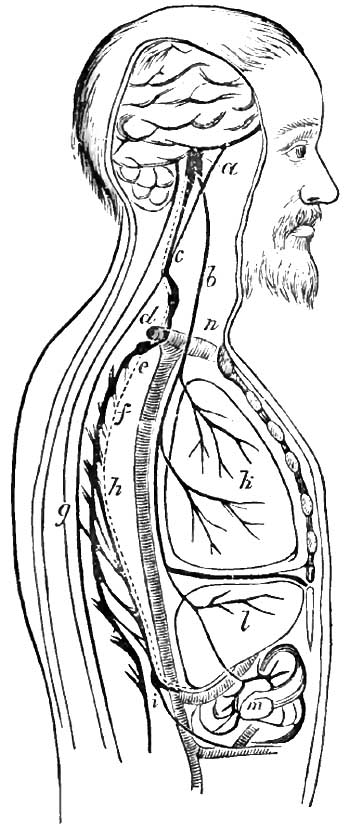

| 3. | DIAGRAM SHOWING COURSE OF THE VASO-MOTOR NERVES OF THE LIVER, ACCORDING TO CYON AND ALADOFF |